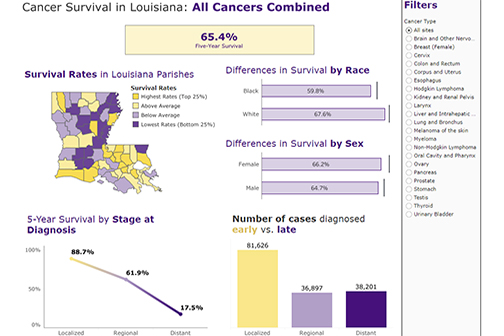

LSU Health New Orleans Releases Latest Report on Cancer in Louisiana

The Louisiana Tumor Registry at LSU Health New Orleans School of Public Health has published Cancer in Louisiana Volume 38. It includes information on cancer incidence and deaths between 2016 and 2020, incidence and mortality trends from 1988 to 2020, survival statistics for cases diagnosed from 2009 to 2019, and followed into 2020, and prevalence of cancer cases diagnosed from January 1, 2000, to January 1, 2020. More

LSU Health’s LA Tumor Registry Publishes Latest Statewide Cancer Incidence, Mortality & Survival Info

LSU Health New Orleans’ Louisiana Tumor Registry has published the latest volume in its annual Cancer in Louisiana monograph series. Cancer in Louisiana, Volume 37, 2015 – 2019, documents cancer incidence and mortality from 2015 to 2019 in Louisiana, as well as incidence and mortality trends from 1988 to 2019. It also includes survival statistics for cases diagnosed from 2008 to 2018 and followed into 2019, as well as prevalence for cancer cases diagnosed from January 1, 2000, to January 1, 2019. More

Latest Cancer in LA Volume Contains New Incidence & Mortality Tables for Industrial Corridor

LSU Health New Orleans School of Public Health’s Louisiana Tumor Registry has published the latest report on cancer incidence and mortality in Louisiana – Cancer in Louisiana 2014-2018 (Volume 36). More